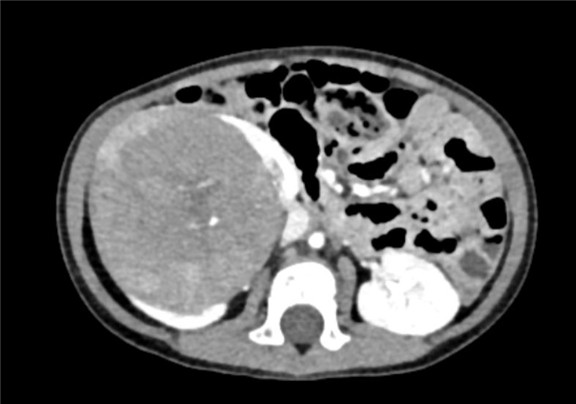

下腹部CT动态增强扫描 肾母细胞瘤化疗后,右肾巨大占位,较前范围减小,请结合临床。

术前CT检查:

动脉期

静脉期

平衡期